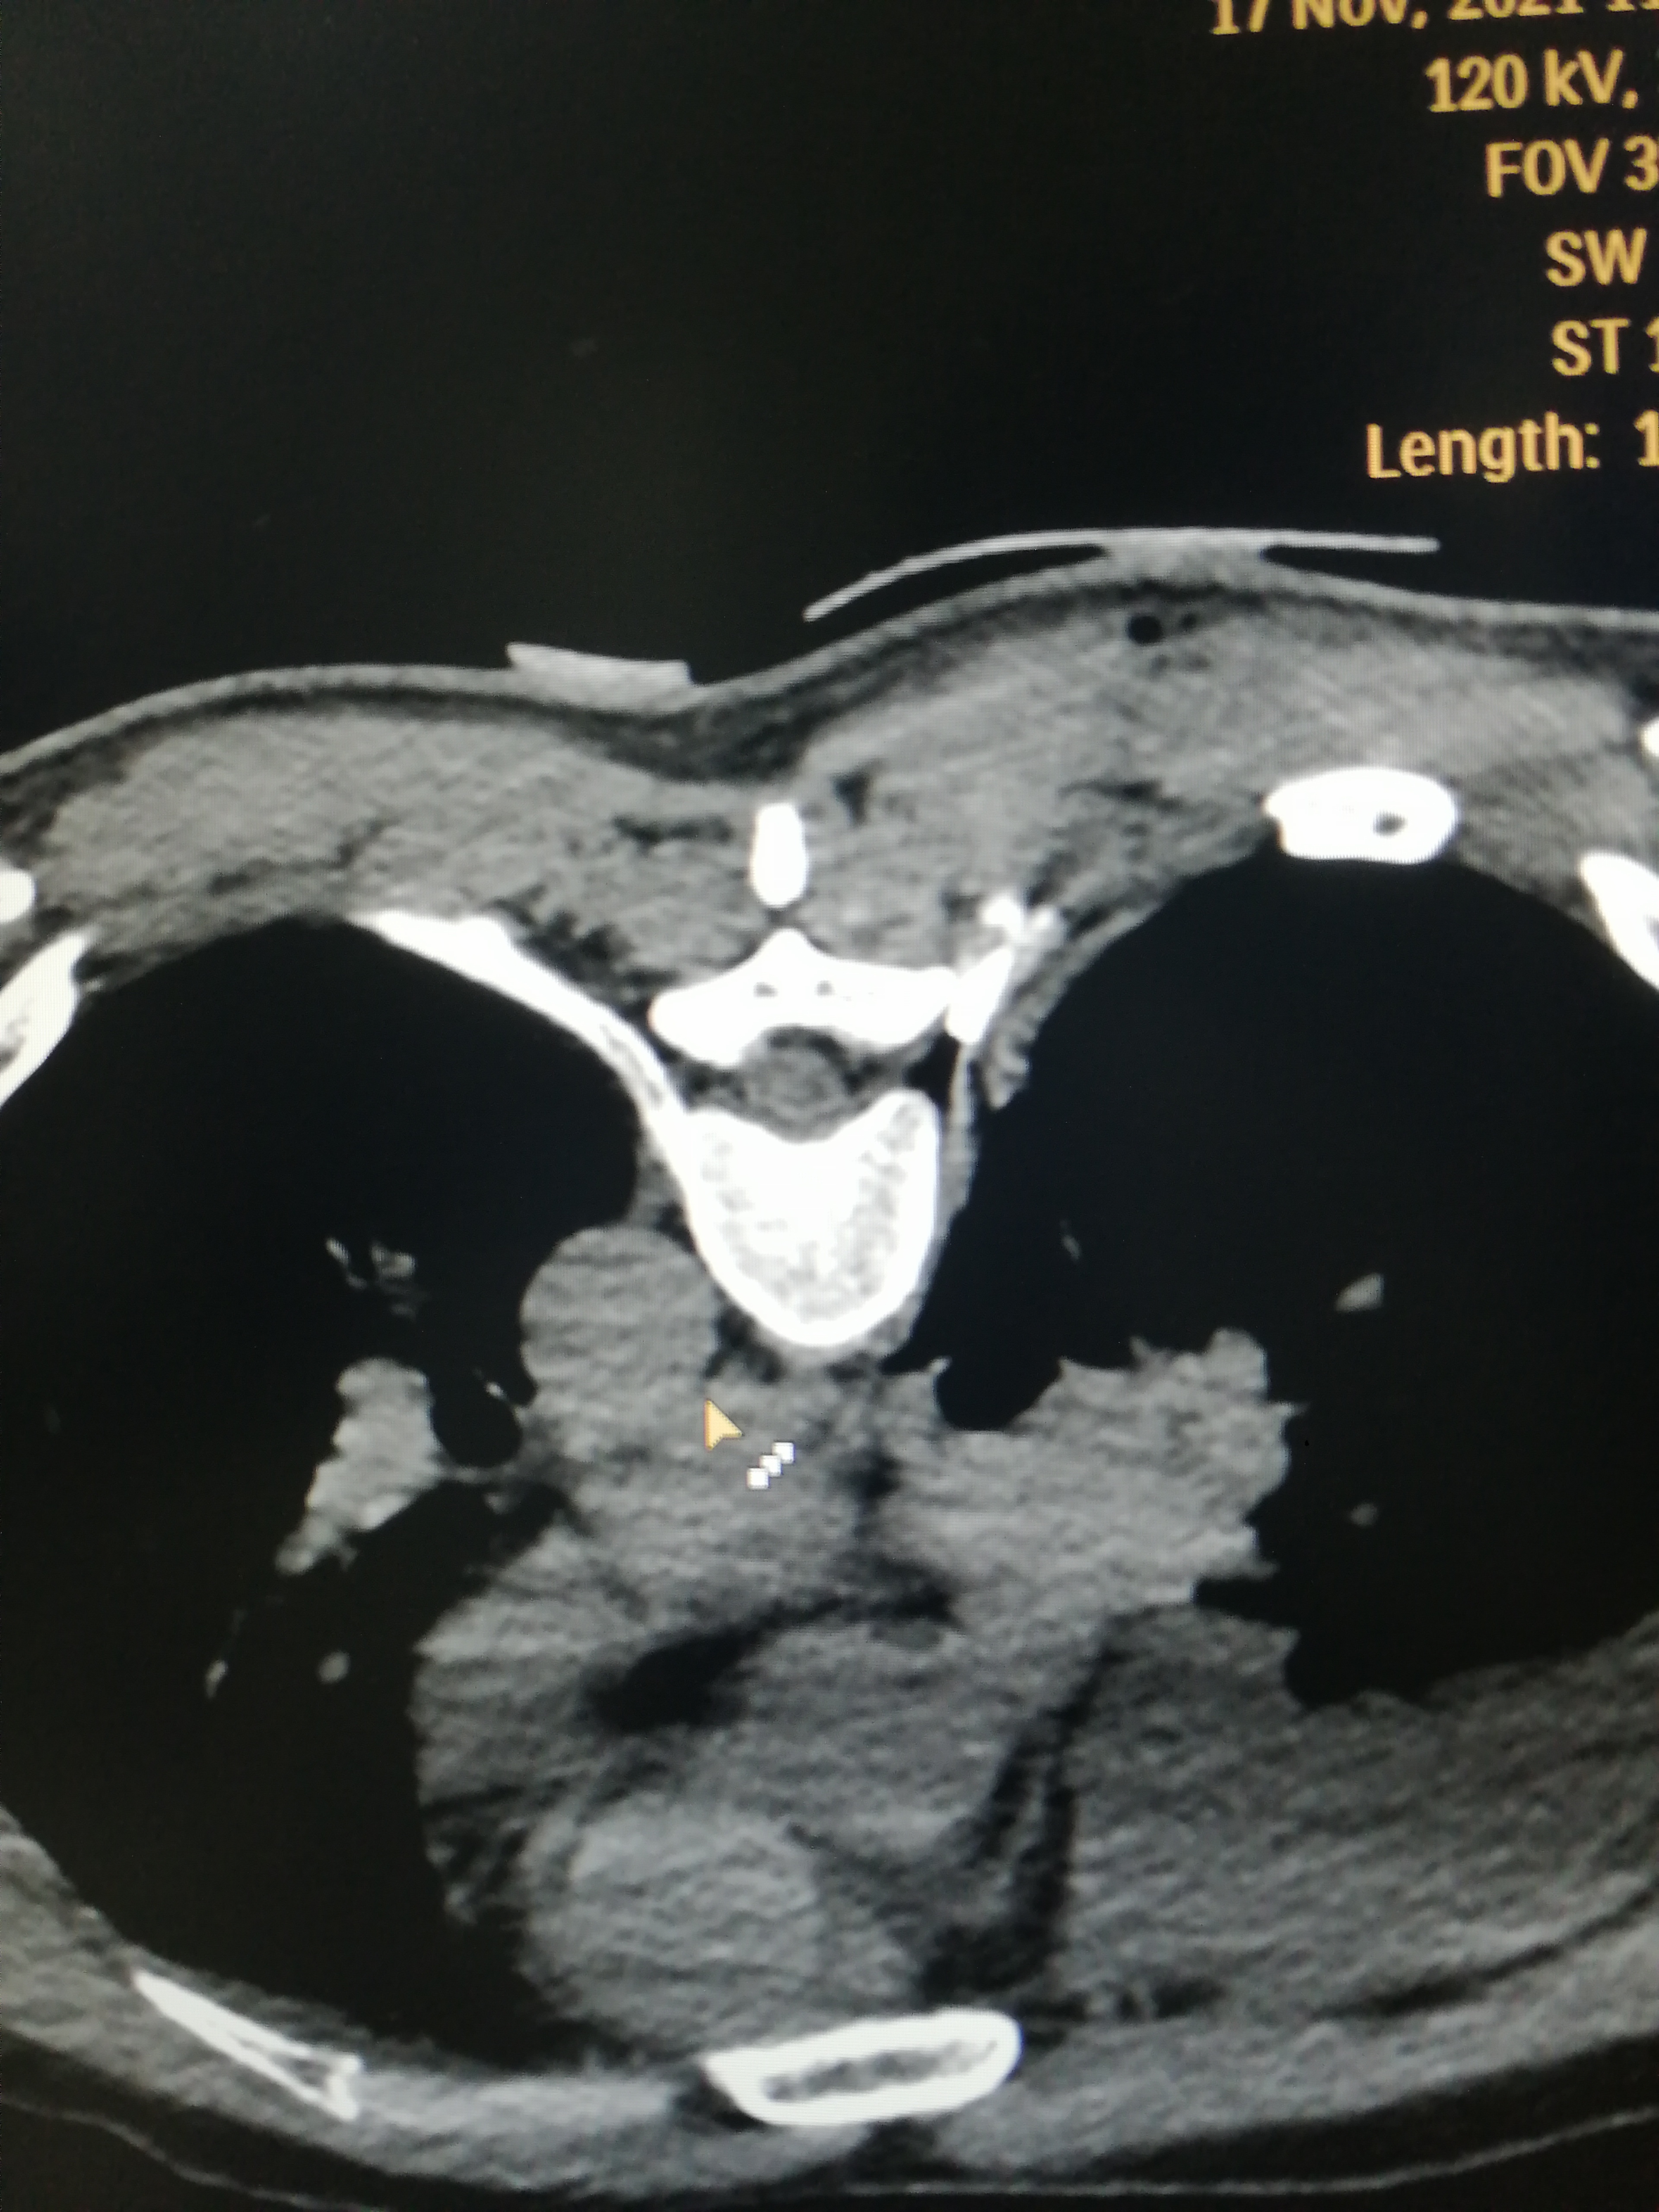

为达成这一目标,田文海主任团队依托该院 3D 打印中心,结合医院先进的大孔径 CT,利用 3D 打印技术可以个体化三维定位引导的优势,为该类患者研制了个体化导板(背根神经节定位穿刺导板),经过多次试验并改进,终于达到了极高的术中定位精准,术中 CT 的引导次数又原来的 5—7 次缩减到 2-3 次。手术时间也缩短到原来的 1/3。